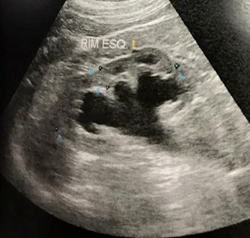

- USG – dilatação bilateral, massa vesical

- Nefrostomia direita com punção guida por USG